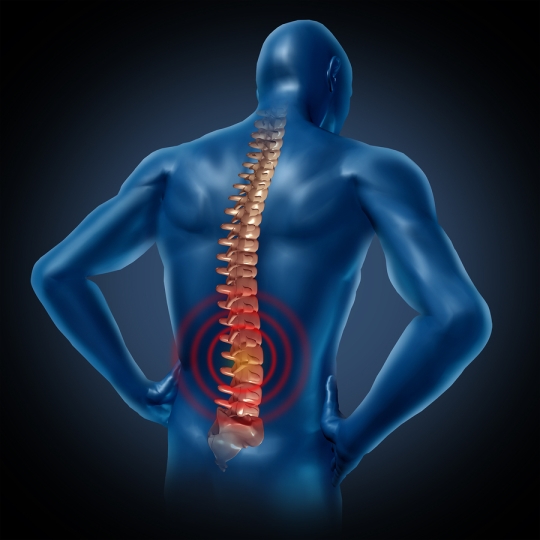

БОЛЬ В СПИНЕ

Коррекция и профилактика всех физиологических параметров, которые касаются правильной осанки позвоночного столба. Таким образом, облегчается боль, вызванная люмбаго, дорсальгией, сколиозом, гиперлоздозом, межпозвоночной грыжей и другими возможными нарушениями.

Лечение и дополнительное укрепление суставных мышц у клиентов, страдающих артритами; восстановление и укрепление мышц после операции; коррекция крылатых лопаток, болезни Шпренгеля, гиперкифоза и другие.